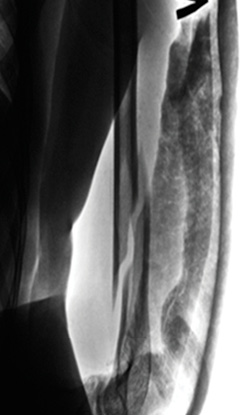

Patient O., 24 years old, visited the trauma department with complaints of pain in the middle third of the left humerus after a fall in the street. On examination, the patient was diagnosed with a closed fracture of the left humerus at the border of the middle and lower thirds with displacement of fragments. The radiograph of the patient’s humerus is presented in Figure 2. Preoperative planning was performed according to the above technique.

Figure 2. X-ray of the left humerus. Closed fracture of the left humerus at the border of the middle and lower thirds with displacement of fragments.

Рисунок 2. Рентгенограмма левой плечевой кости. Закрытый перелом левой плечевой кости на границе средней и нижней третей со смещением отломков.